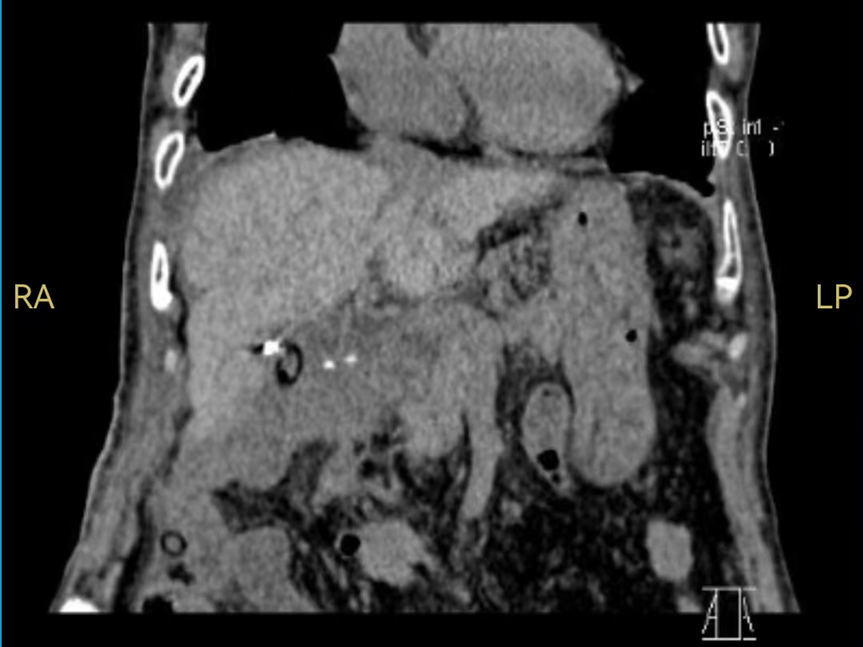

已90岁高龄的洪老太太,被突如其来的腹部剧痛袭击,急诊入院检查发现她的肝门区有一个7.1厘米的巨大肿瘤,并不幸发生自发性破裂,导致内出血,情况十分凶险。

尽管手术困难重重大,在肝胆胰医学中心王耀东教授、田毅峰教授带领下,陈忠副主任医师团队缜密评估,组织麻醉科、重症医学科、手术室等多学科讨论,最终制定完整的手术、麻醉及术后诊治方案。术中,团队在肝门区附近精雕细琢保护重要的入肝血管主干并完整切除肝癌病灶,吸尽周边积血并冲洗干净。术后老人顺利复苏,令人振奋的是,她在术后短时间内就恢复到生病前的状态。